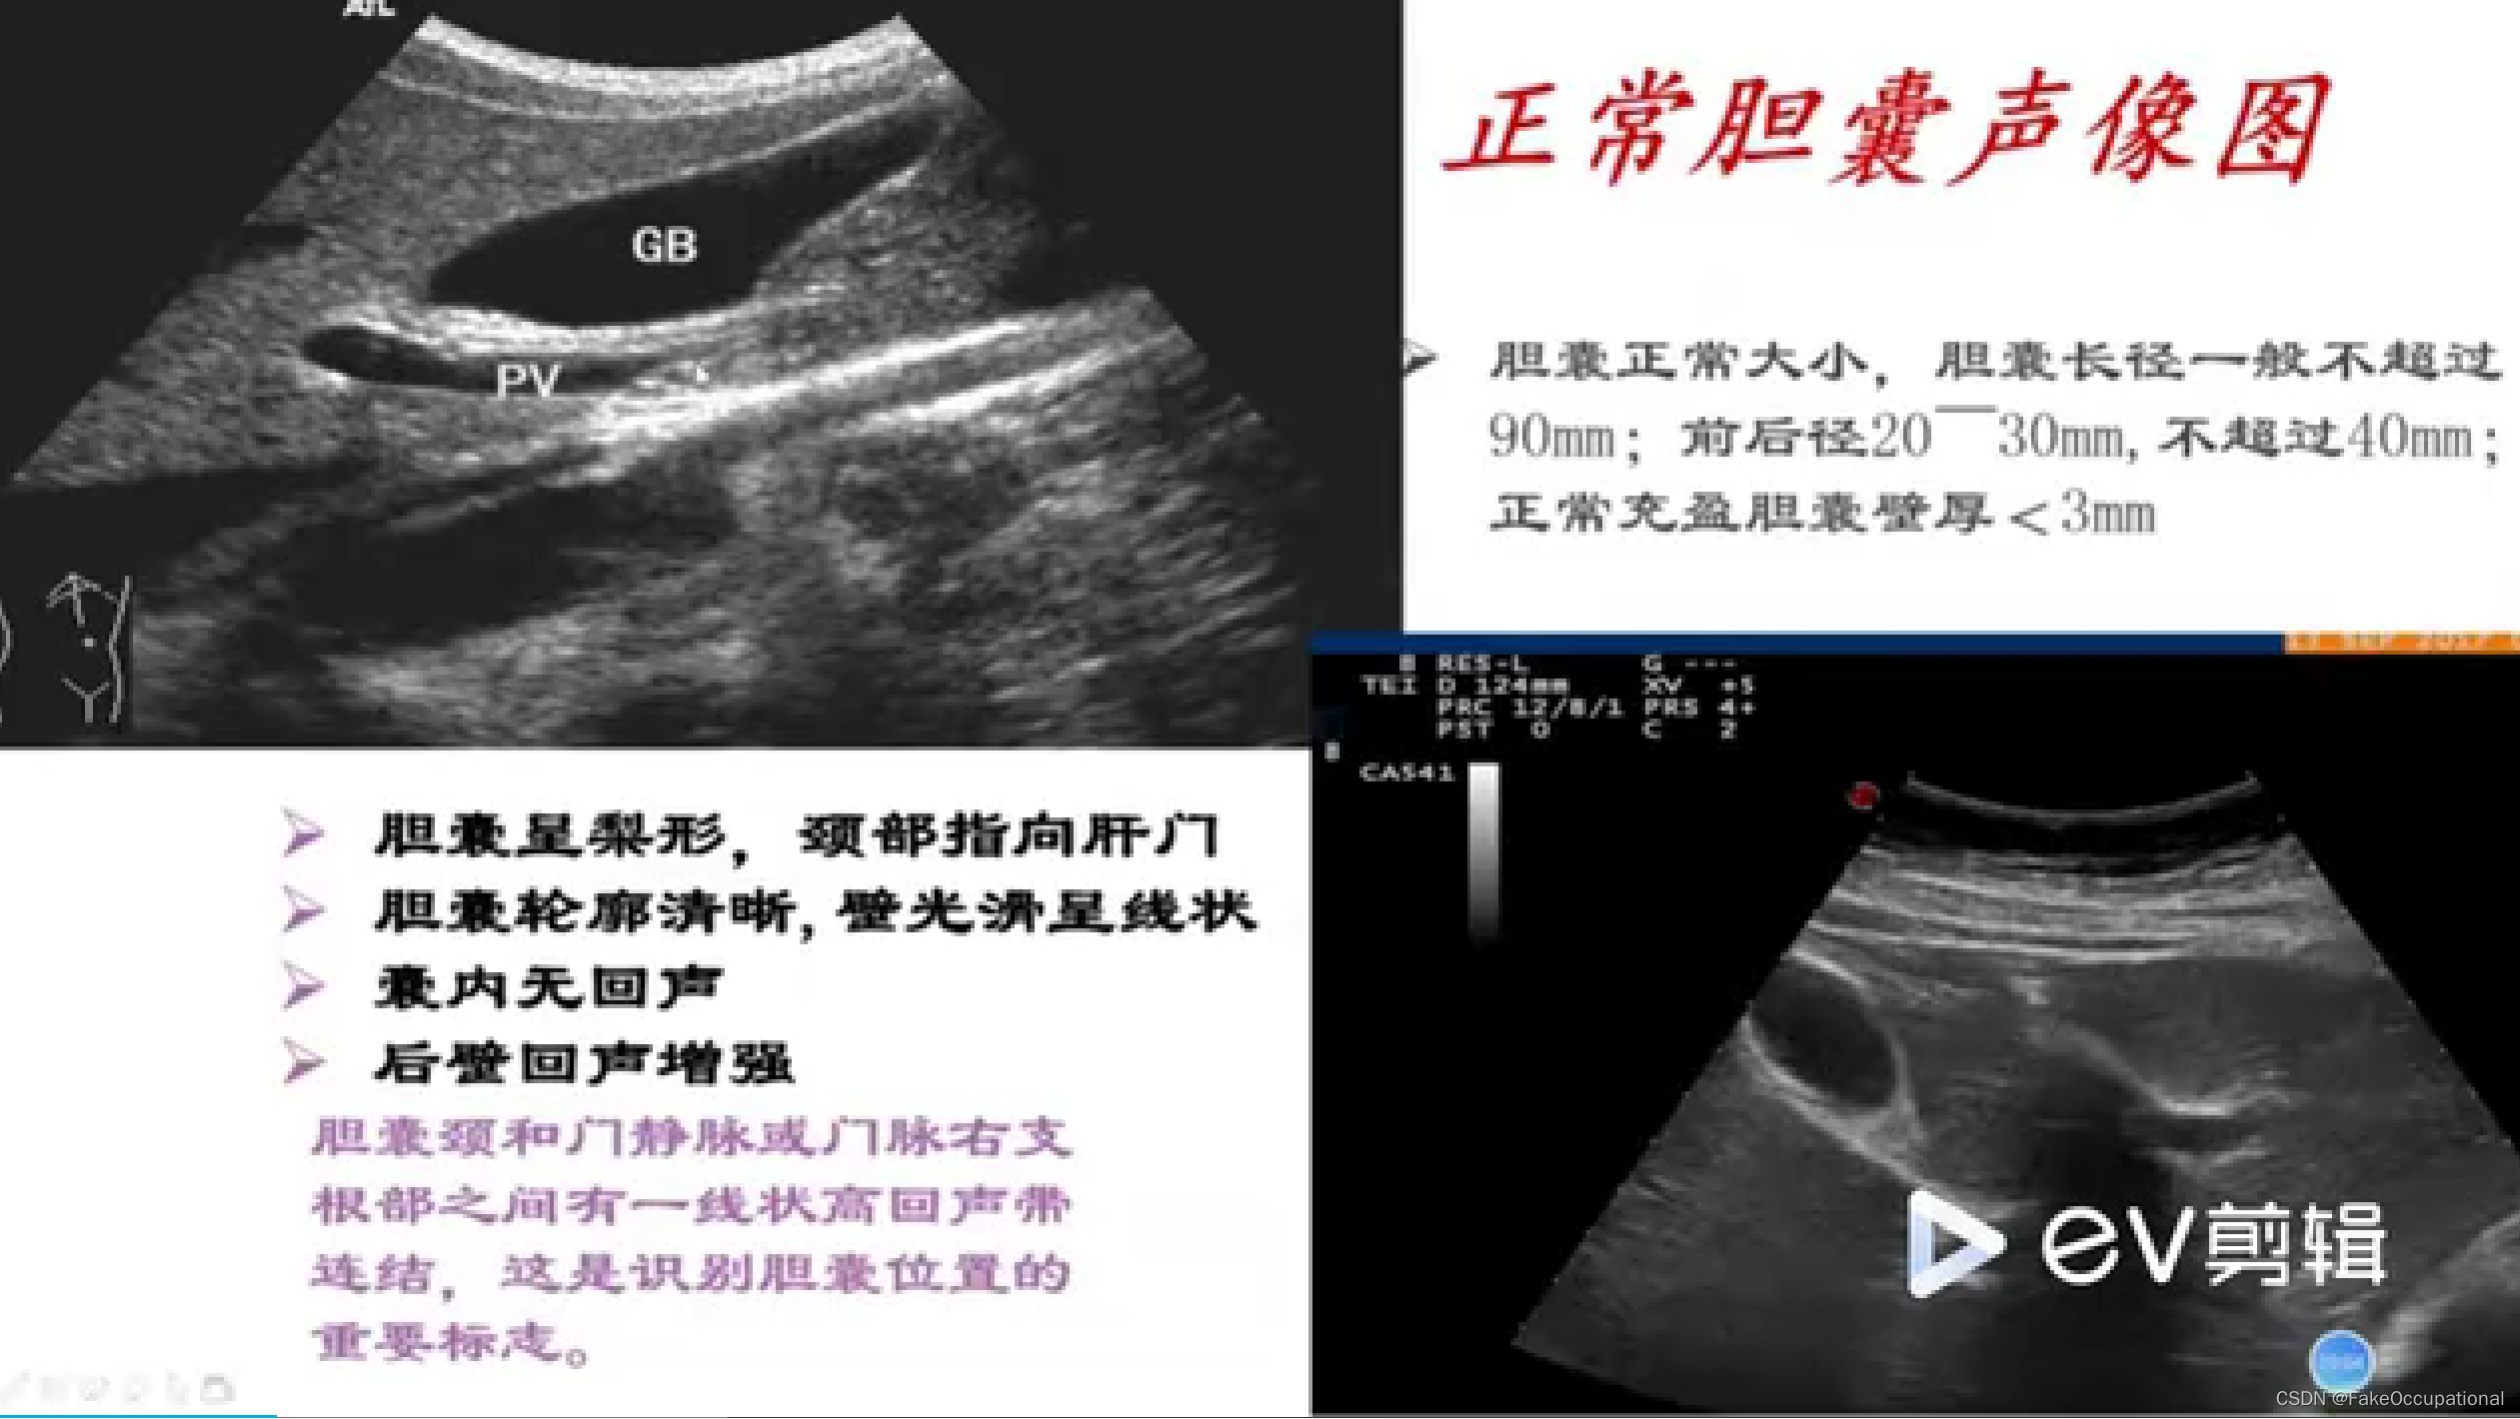

正常胆囊及胆管声像图

- 下边紫框中为正常胆囊